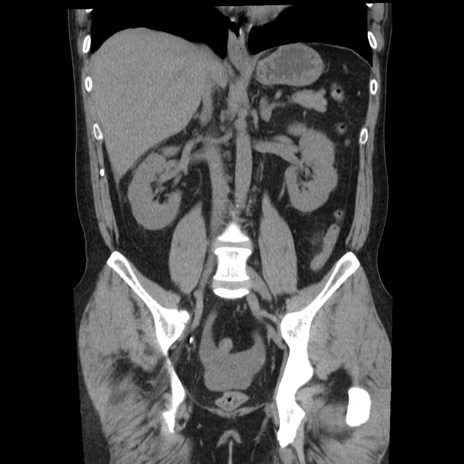

横断像